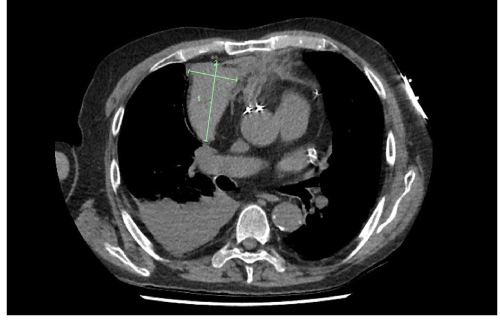

Mediastinal haemorrhage caused by rupture of a saphenous vein coronary artery bypass graft (CABG) is a potentially life-threatening complication following the grafting procedure...